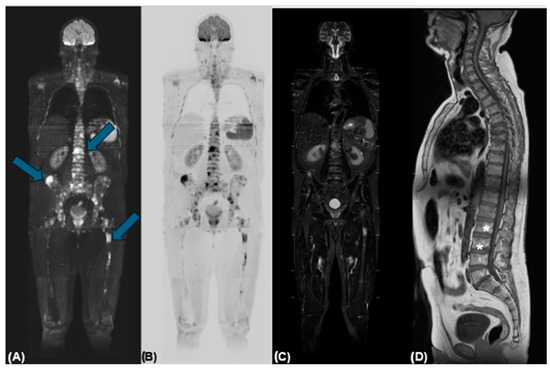

A Rare Case of Primary Bone Follicular Lymphoma with Multiple Osteolytic Lesions: A Case Report and Review of the Literature

Togni, C.; La Verde, G.; Pelliccia, S.; Bianchi, M.P.; Di Napoli, A.; Lanzolla, T.; Zerunian, M.; Laghi, A.; Maiorana, G.; Taglietti, A.; et al. A Rare Case of Primary Bone Follicular Lymphoma with Multiple Osteolytic Lesions: A Case Report and Review of the Literature. Hemato 2024, 5, 388-395. https://doi.org/10.3390/hemato5040028